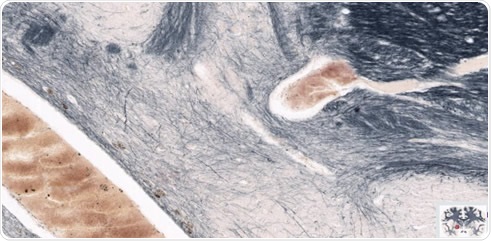

The brain in figure 1 magnified to highlight regions of interest in the left hemisphere.

Figure 2. The brain in figure 1 magnified to highlight regions of interest in the left hemisphere. Image credit: Huron Digital Pathology.